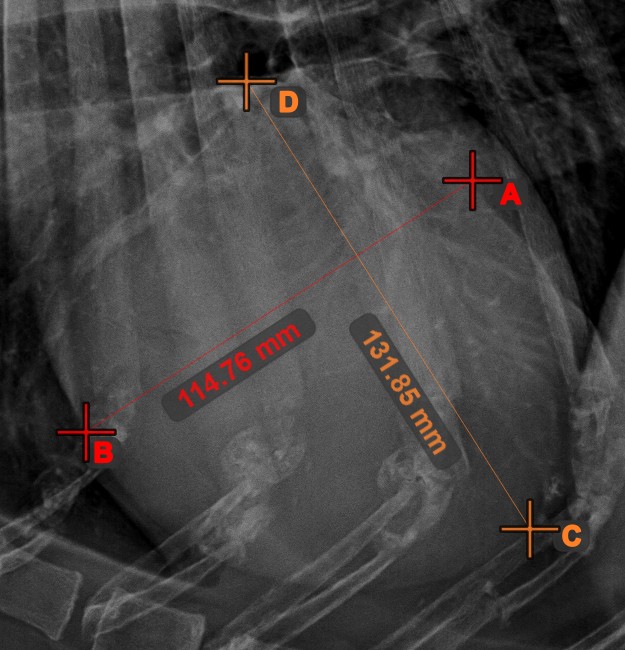

Line Measurement

Create a line measurement to calculate the distance between two points with high precision.

Select the Line Measurement tool and assign it to one of the available mouse buttons. Place the start and end points on the scene or select them from already existing points on the image. The distance between the two points will be automatically calculated by using the default calibration data, or the recalibrated data by the length calibration measurement.

Modify the start and end point by using the Select/Move Item tool. The distance between the two points will be automatically recalculated.

../_images/image164.jpg